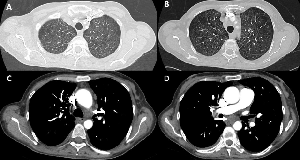

Lung transplantation is an established treatment option for well-selected patients with end-stage pulmonary disease, when other therapeutic options are no longer available. Although the post-transplant survival has much improved in recent years, the development of chronic lung allograft dysfunction (CLAD), which affects 40–50% of all patients by 5 years post-transplant, remains the major cause of morbidity and mortality [1]. CLAD is defined by a progressive and persistent decline in the forced expiratory volume in the first second (FEV1) of at least 20% compared to the postoperative best value. Several different phenotypes of CLAD have been identified, based on the physiology of the lung function decline, such as obstructive (bronchiolitis obliterans syndrome, BOS), restrictive (restrictive allograft syndrome) or a combination (mixed phenotype), along with the presence or absence of persistent opacities on chest imaging [2, 3].